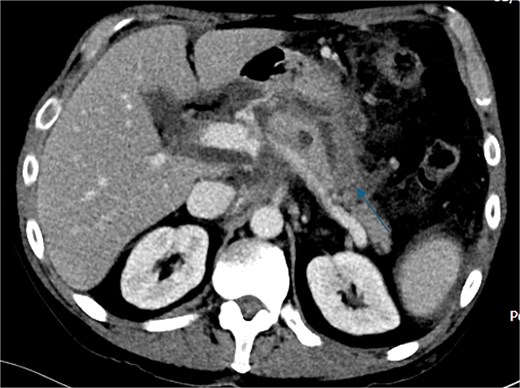

Despite the absence of abdominal symptoms, a computed tomography of the abdomen and pelvis (CTAP) was performed due to markedly elevated lipase levels. The CTAP (Figs 3–5) revealed evidence of acute pancreatitis (Fig. 5, arrow), with a complex peripancreatic fluid collection (Fig. 3, arrow). Additionally, a focal thrombus was observed within the portal venous confluence (Fig. 4, arrow). Further ultrasound of the gallbladder was negative for gallstones (Fig. 6), ruling out gallstone-induced pancreatitis.

CTAP coronal view; complex peripancreatic fluid collection (arrow) with extension behind the splenic vein to lie adjacent to the pancreatic neck and uncinate process.